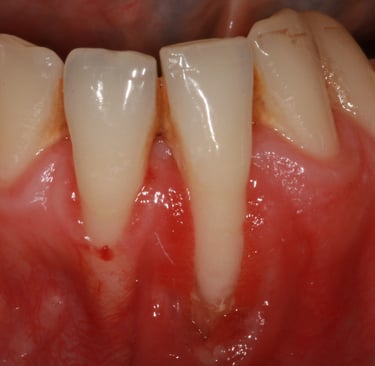

Le recessioni gengivali sono una condizione comune in cui il tessuto gengivale si ritira, esponendo una parte del dente o della radice. Questo problema non è solo estetico, ma può anche compromettere la salute orale.

Denti che sembrano più lunghi

Sanguinamento durante lo spazzolamento